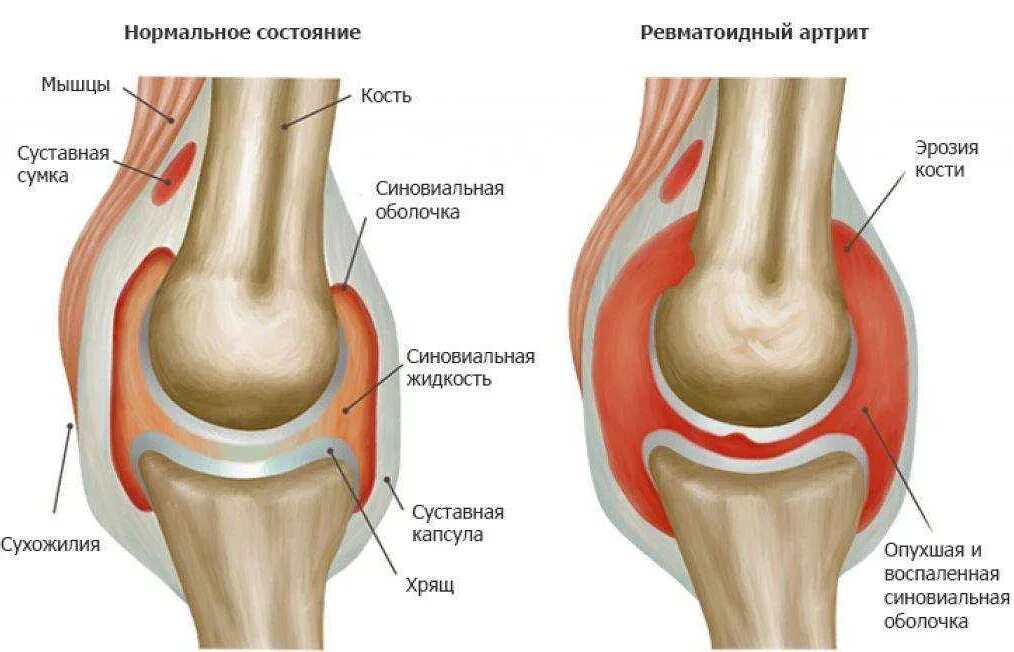

Как лечить синовит тазобедренного сустава